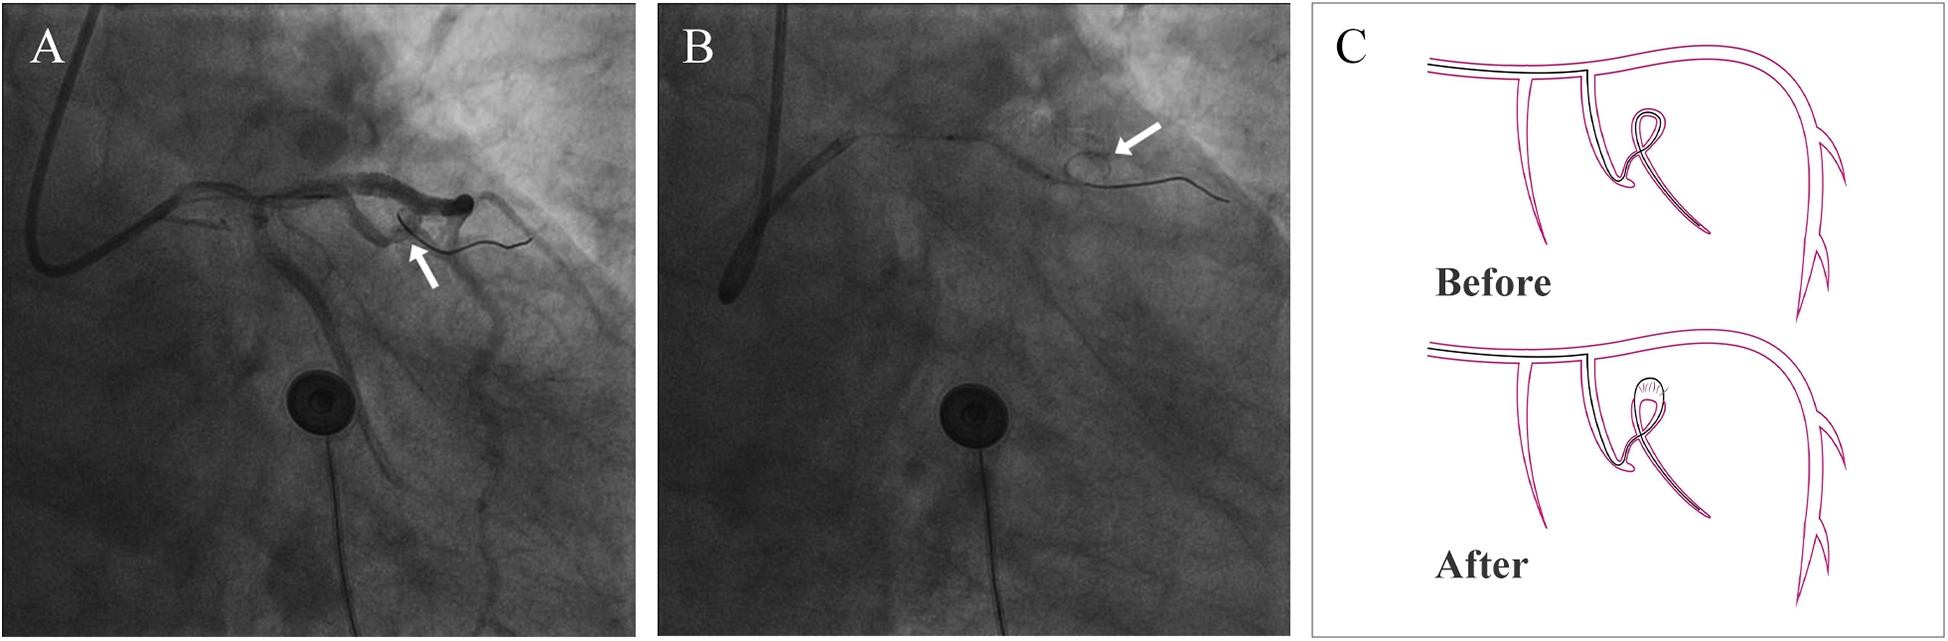

Figure 2

Coronary artery perforation. (A) The arrow points to the coiled guidewire before coronary artery rupture (B) the arrow points to the coiled guidewire after coronary artery rupture (C) schematic diagram of guidewire cutting the coronary artery.